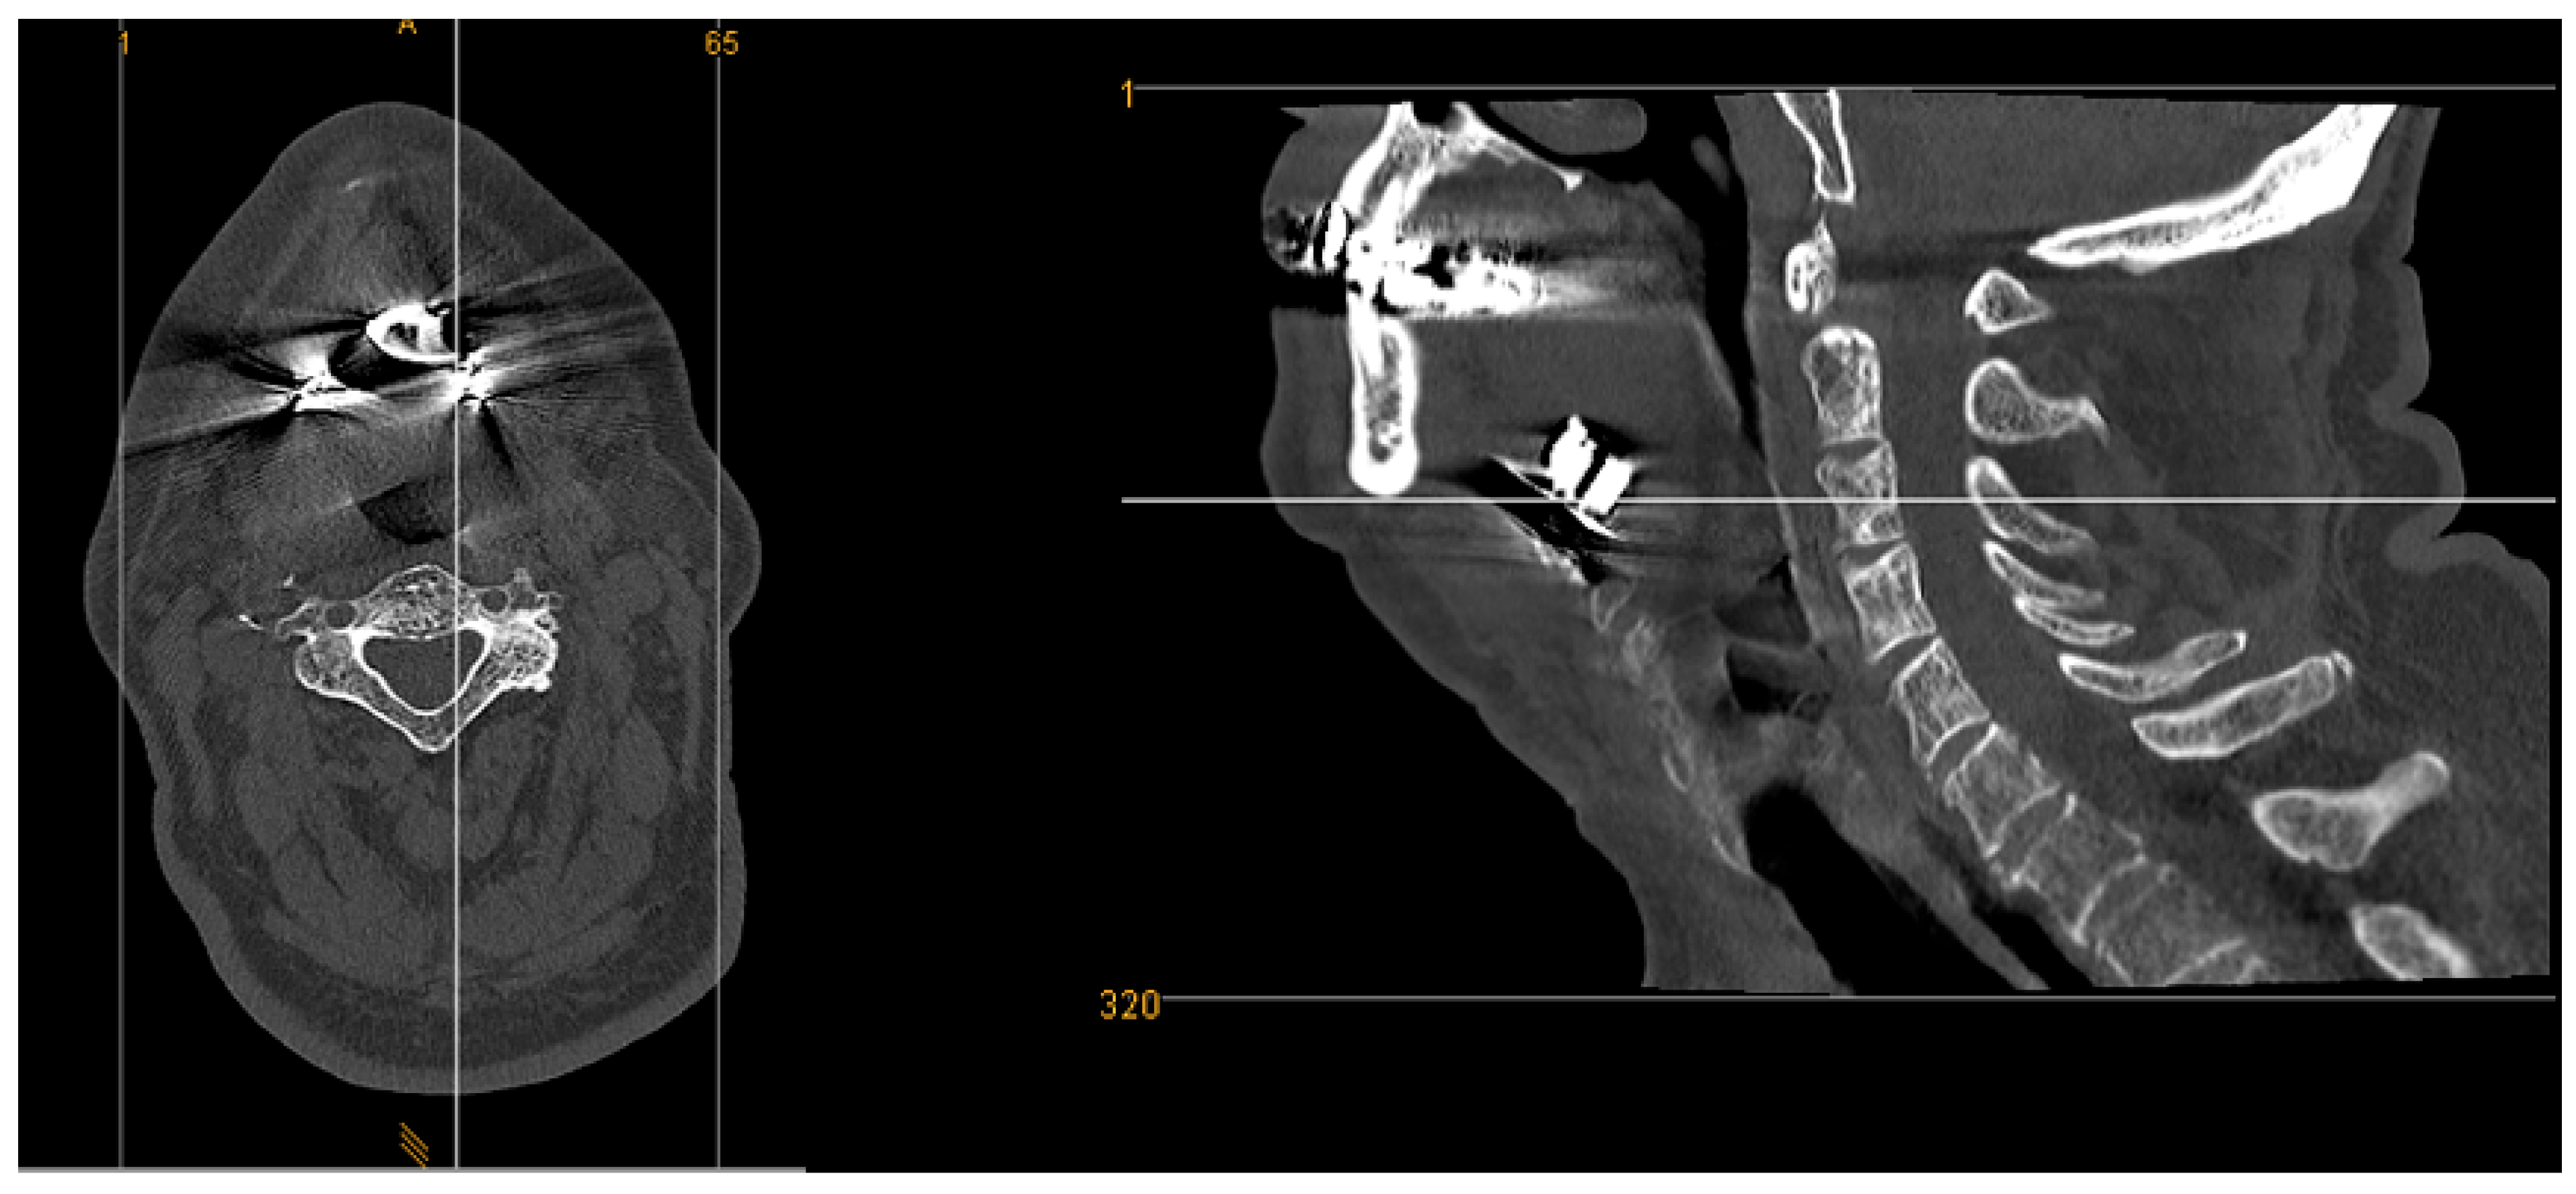

| 1 | 33 | 26 | yes | yes | yes | moderate | no | yes | 87,3 | 28,7 | 56,4 | 15,2 | 7,9 | 22,6 | -14,7 | asymmetry | 64,9 | proximal | proximal |

| 2 | 47 | 30 | yes | yes | yes | strong | no | yes | 94,1 | 45,7 | 57,0 | 19,0 | 18,7 | 19,3 | -0,6 | symmetry | 70,4 | proximal | proximal |

| 3 | 51 | 28 | yes | no | n/a | n/a | no | yes | 109,3 | 32,6 | 48,4 | 17,2 | 15,0 | 19,3 | -4,3 | asymmetry | 60,3 | proximal | proximal |

| 4 | 64 | 31 | yes | yes | yes | moderate | no | yes | 113,9 | 55,3 | 76,2 | 25,9 | 18,8 | 32,9 | -14,1 | asymmetry | 73,8 | proximal | proximal |

| 5 | 37 | 32 | yes | yes | yes | strong | no | yes | 93,2 | 23,9 | 54,5 | 15,4 | 13,9 | 16,9 | -3,0 | asymmetry | 35,3 | proximal | proximal |

| 6 | 52 | 25 | yes | yes | yes | moderate | no | yes | 86,0 | 20,3 | 47,1 | 15,8 | 15,6 | 16,0 | -0,4 | symmetry | 19,0 | proximal | distal |

| 7 | 28 | 28 | yes | yes | yes | moderate | no | yes | 102,0 | 36,7 | 64,3 | 16,4 | 14,4 | 18,3 | -3,8 | asymmetry | 40,7 | proximal | distal |

| 8 | 16,5 | 34 | yes | yes | yes | strong | no | yes | 122,3 | 32,1 | 77,9 | 12,5 | 18,4 | 6,6 | 11,8 | asymmetry | 39,9 | proximal | distal |

| 9 | 32 | 29 | yes | yes | yes | moderate | no | yes | 110,5 | 40,3 | 69,4 | 16,6 | 14,9 | 18,2 | -3,2 | asymmetry | 63,5 | proximal | proximal |